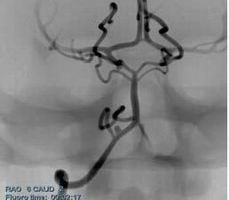

顱內(nèi)血管介入手術(shù)模塊

訓(xùn)練醫(yī)生進(jìn)行顱內(nèi)動脈瘤可脫彈簧圈栓塞術(shù)、顱內(nèi)動脈狹窄治療等手術(shù)操作